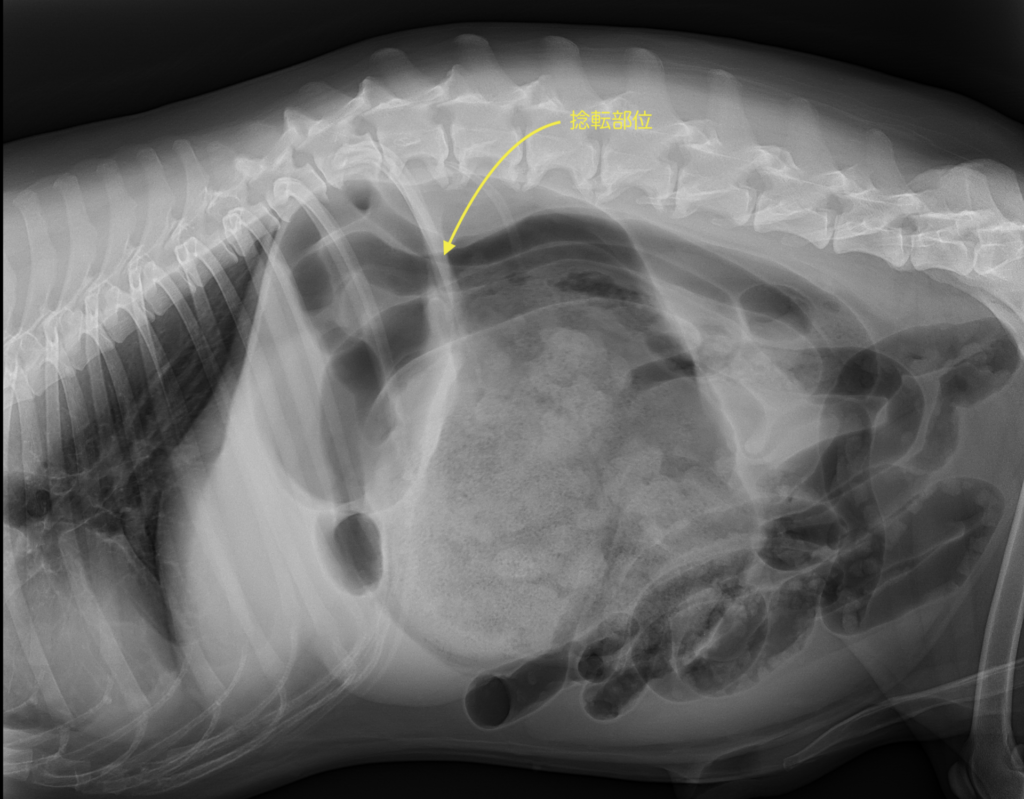

胃拡張捻転症候群を疑った際は、第一にレントゲンを撮影します。その後状態の把握のために血液検査、血圧測定、心電図検査、エコー検査を追加します。下の写真は胃拡張を起こし、捻転まで至った画像になります。